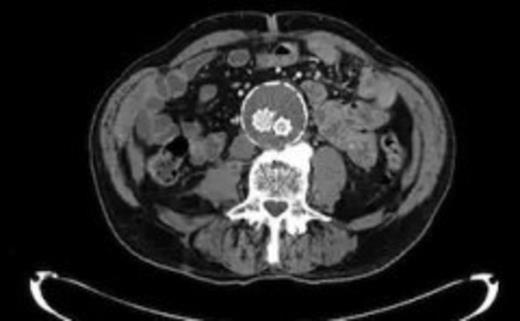

Four weeks following discharge the patient was re-admitted with feeling increasingly unwell, recurrent pyrexia, loss of appetite and mild shortness of breath on exertion. Physical examination was unremarkable except for a temperature of 38.3 centigrade. Blood tests on admission showed Hb 11.4 g/dl (11.5-16.0 g/dl), white cell count 13.1×109/L (4-9.2 x 109/L) and CRP 68mg/L (<3 mg/L). Contrast enhanced CT scan (Fig. 2,3) showed a 50 mm maximum retroperitoneal collection situated between the right kidney and the right iliac vessels. It contained a few loculi of gas. A diagnosis of postoperative right psoas abscess was made. The patient was started on intravenous broad spectrum antibiotics – Tazocin (Piperacillin+ Tazobactam) and Metronidazole. CT guided drainage was carried out using a 10 French gauge pigtail catheter locked pigtail (Meditech Flexima regular all-purpose drainage catheter sets with locking pigtail (Boston Scientific)) (Fig. 4). The isolation of E. coli from the collection with negative Hemocultures suggested a bowel source for the infection but no actual breach was demonstrable. The bowel surgeons ruled out colonic pathology.

A 50 mm maximum retroperitoneal collection situated between the right kidney and the right iliac vessels